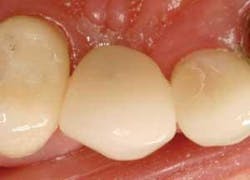

Figure 18 - Oblique view of the completed case. Completed crown from facial view using the 1M2C Triluxe ceramic block material (Vita). Yellow MultiLink cement (Ivoclar Vivadent) was used to bond the crown to the metal abutment.